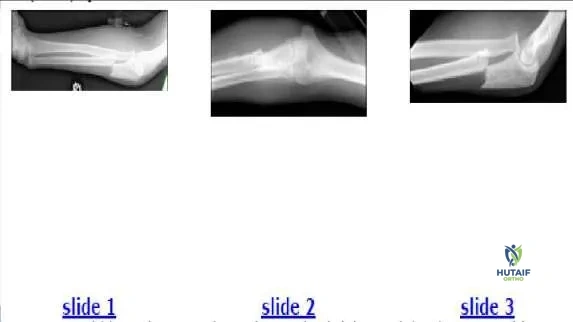

The 12-year-old boy shown in the radiographs (Slide 1, Slide 2) sustained his injury during a motor vehicle accident. Which of the following most accurately describes the injury:

Correct Answer: Type 1 Monteggia fracture

This patient has a proximal ulna fracture and an anterior dislocation of the radial head. The ulna-trochlea relationship is intact. On the lateral film, the

radial head does not articulate with the capitellum. On the anteroposterior film, the radial head points to the capitellum, but the joint space is absent in contrast to that of the ulna-trochlear joint, which is normal. This injury is a type 1 (anterior) Monteggia fracture. The dislocation is clearly visible on Slide 3. A Galeazzi fracture refers to a distal radioulnar dislocation with a radial fracture. A Maisonneuve fracture is a related concept in the lower extremity: a proximal fibular fracture with an ankle mortise injury.